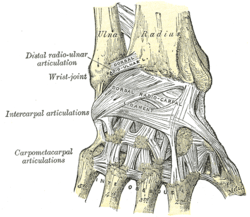

Ligaments of wrist. Posterior view. | |

Ligaments

These four CMC joints are supported by strong transverse and weaker longitudinal ligaments: the dorsal carpometacarpal ligaments and the volar or palmar carpometacarpal ligaments.[7]

The interosseous ligaments consist of short, thick fibers, and are limited to one part of the carpometacarpal articulation; they connect the contiguous inferior angles of the capitate and hamate with the adjacent surfaces of the third and fourth metacarpal bones.